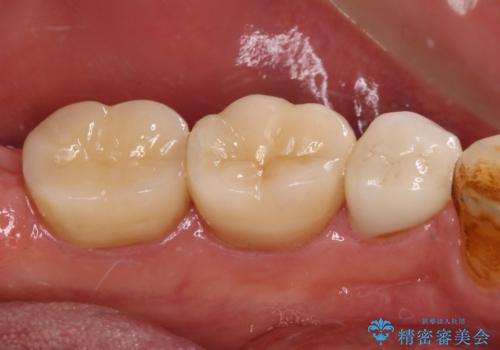

虫歯を取り除き、仮歯を装着した時点でしみる感覚は改善されました。

オールセラミッククラウン装着後も経過は良好です。